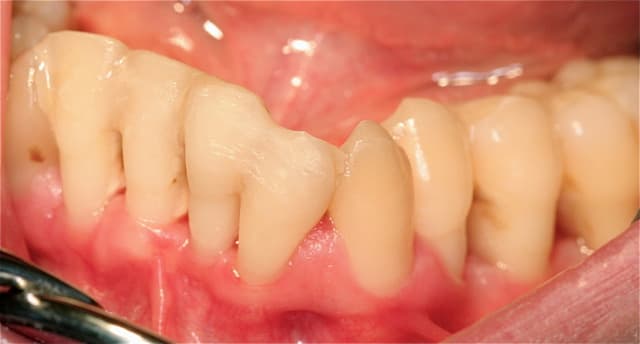

je peux vous soumettre quelques clichés, je crois intéressants ...j'ai investit dans du matériel photo pour vous séduire, acheté des habits sérieux...

toujours aucune extractions depuis 8 ans, sur des cas de paro nommé irréparable par les plus grands parodontistes de France et de suisse! LOL

lus de 250 cas extrêmes et difficiles traités prouvent que nous sommes bien en présence d'une blessure souillée et qu'il suffit de la traiter comme toute blessure souillée.

Les photos que tu montres ne donnent aucun renseignement quand à la guérison du parodonte (Ah oui , pardon ce n'est pas une maladie ).

tes contentions sont dégueulasses même sur des photos de mauvaise qualité peu importe qu'elles soient linguales ou vestibulaires c'est un rail de composite point barre !